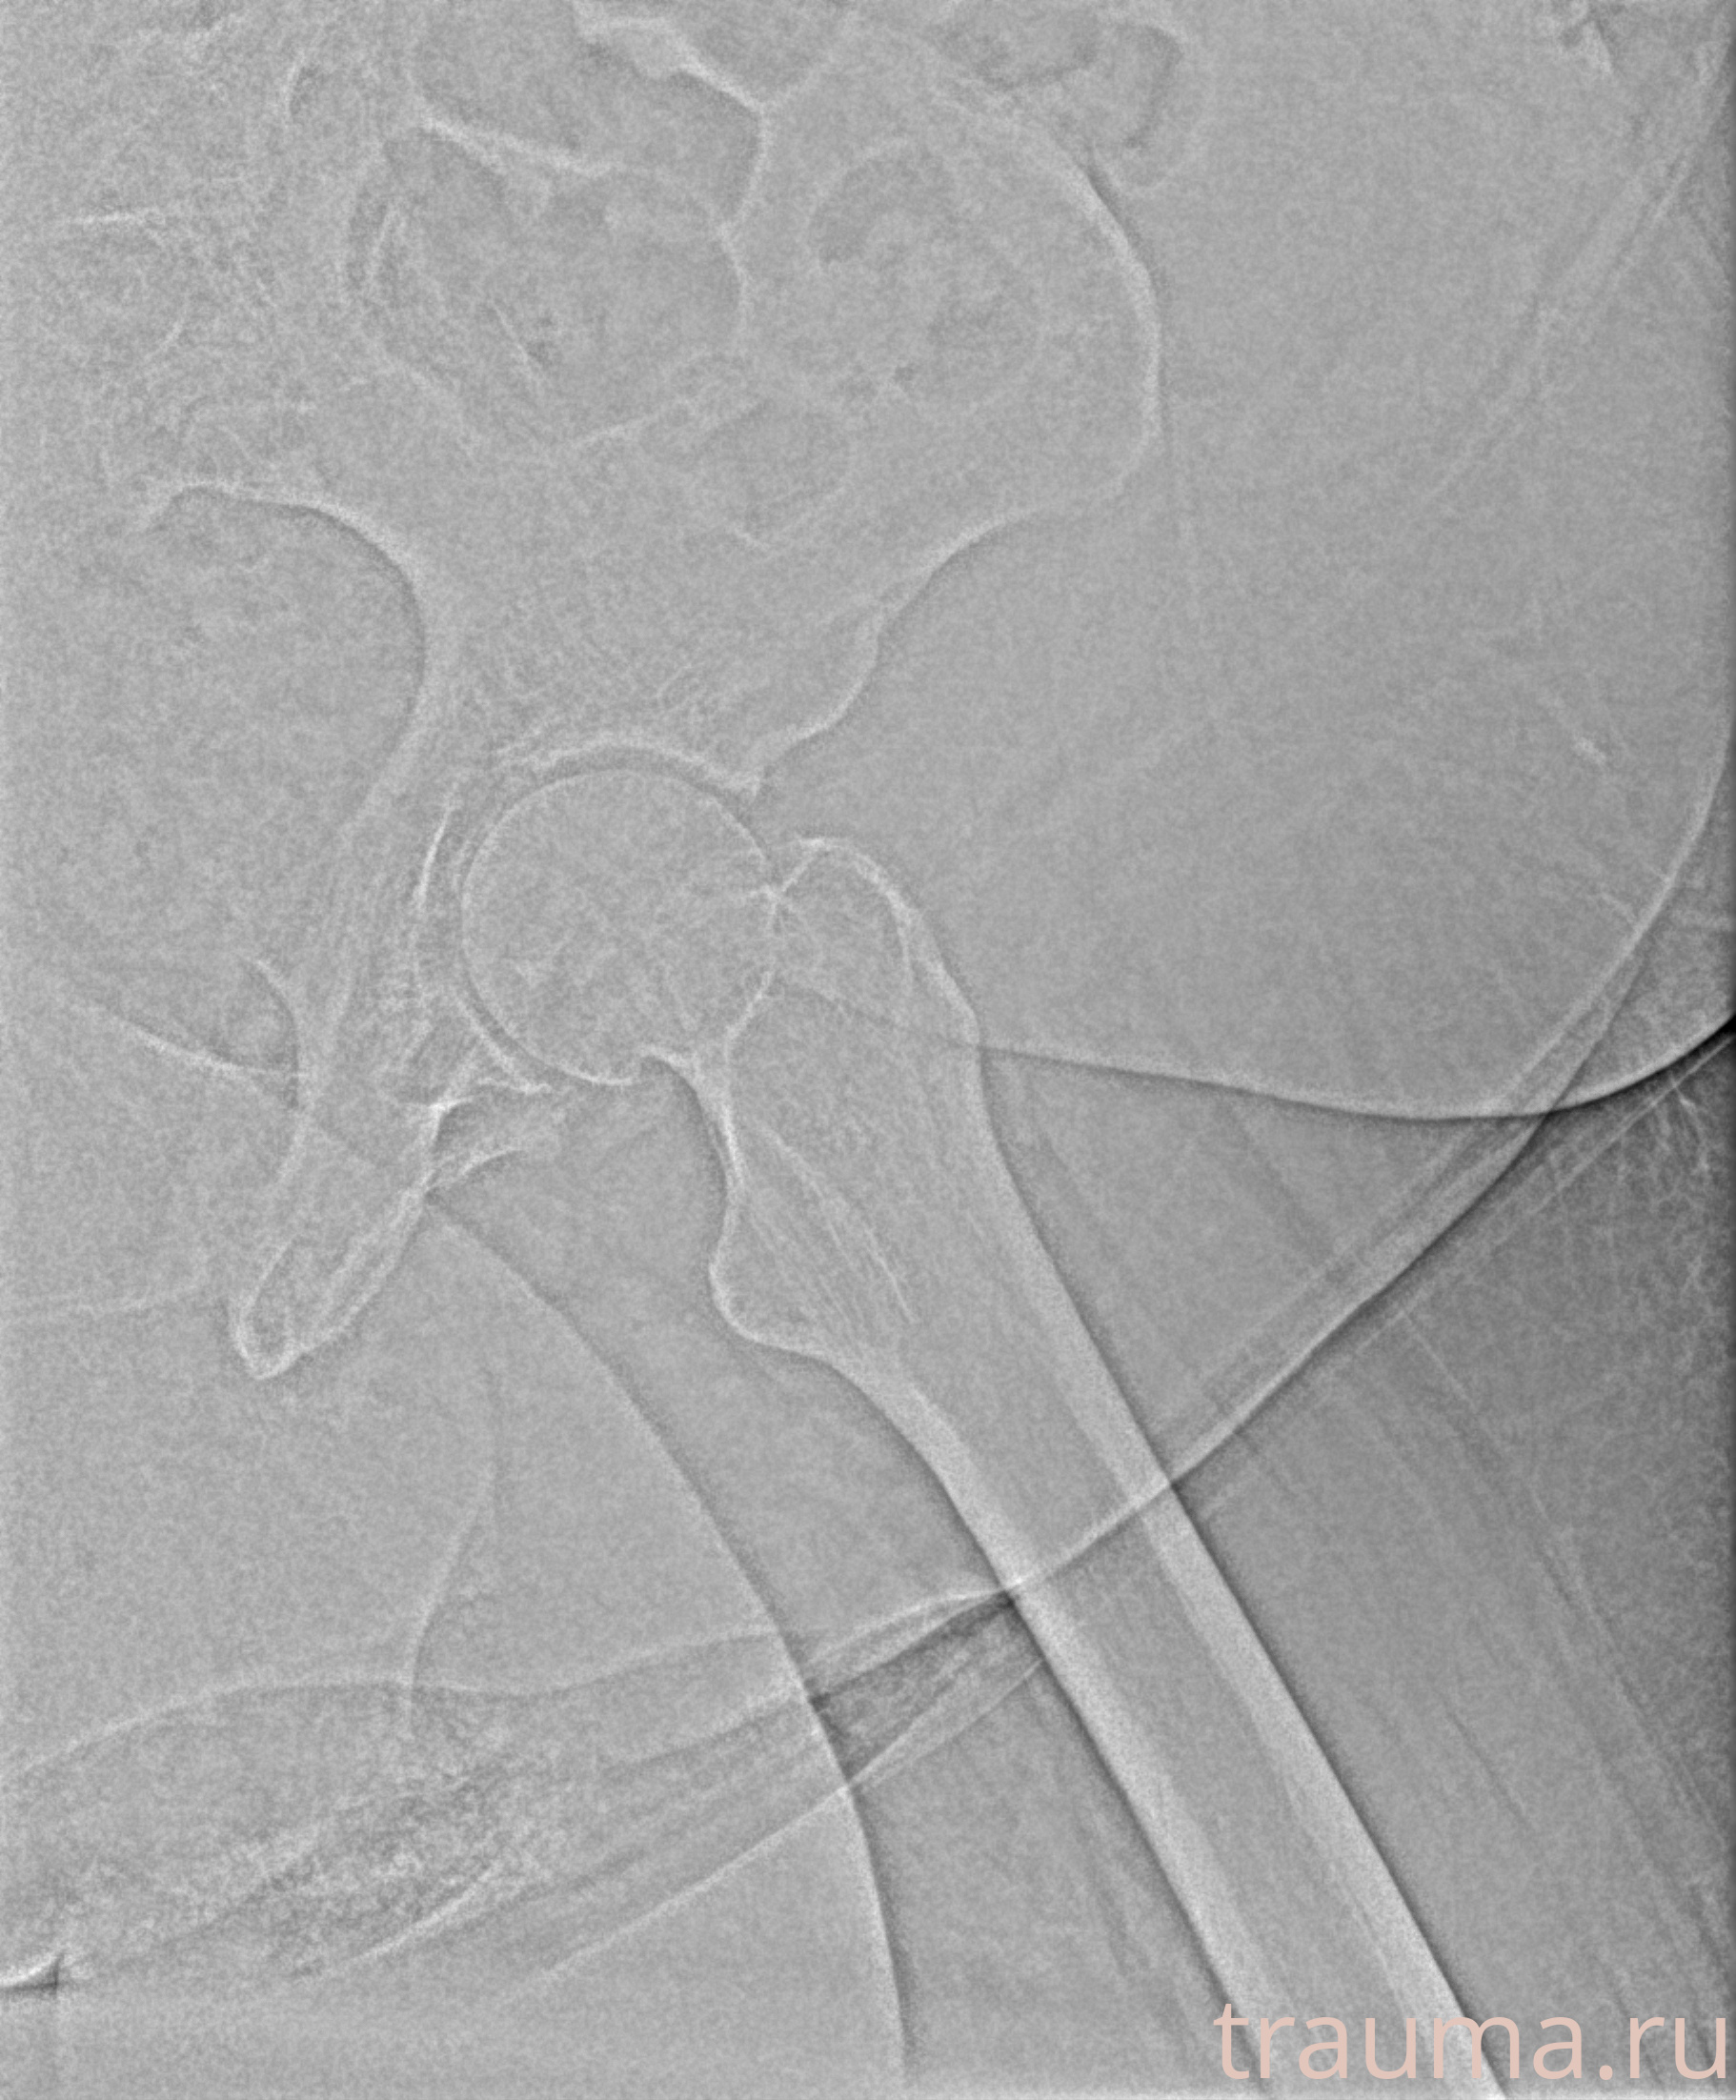

Первая помощь при переломе шейки бедра

Рентген на дому: по вашему адресу приезжает врач-рентгенолог, травматолог-ортопед с мобильным рентгеновским аппаратом, проводит диагностику травмы или заболевания, делает необходимые рентгенограммы, дает рекомендации по дальнейшему лечению. Получить качественные снимки в домашних условиях возможно благодаря уникальной методике, разработанной МосРентген Центром для института  Склифосовского